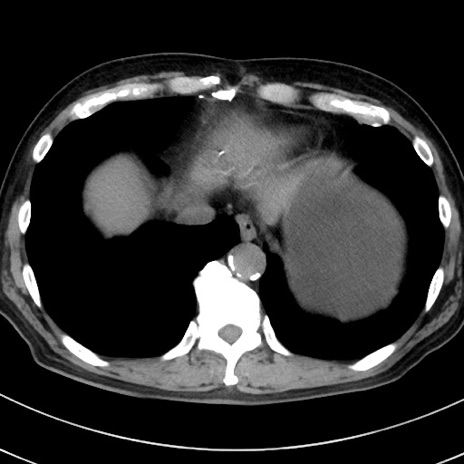

症例38(横断像)

【症例】70歳代 男性

【主訴】腹痛・嘔吐

【現病歴】昨晩より、嘔吐・腹痛あり。今朝になっても嘔吐あり。来院。

【既往歴】心臓バイパス手術、開腹胆摘、腸閉塞

【身体所見】BP 107/71mmHg、HR 116/min、腹部:平坦、軟、下腹部に軽度圧痛あり。反跳痛なし。

【データ】WBC 15100、CRP 0.32